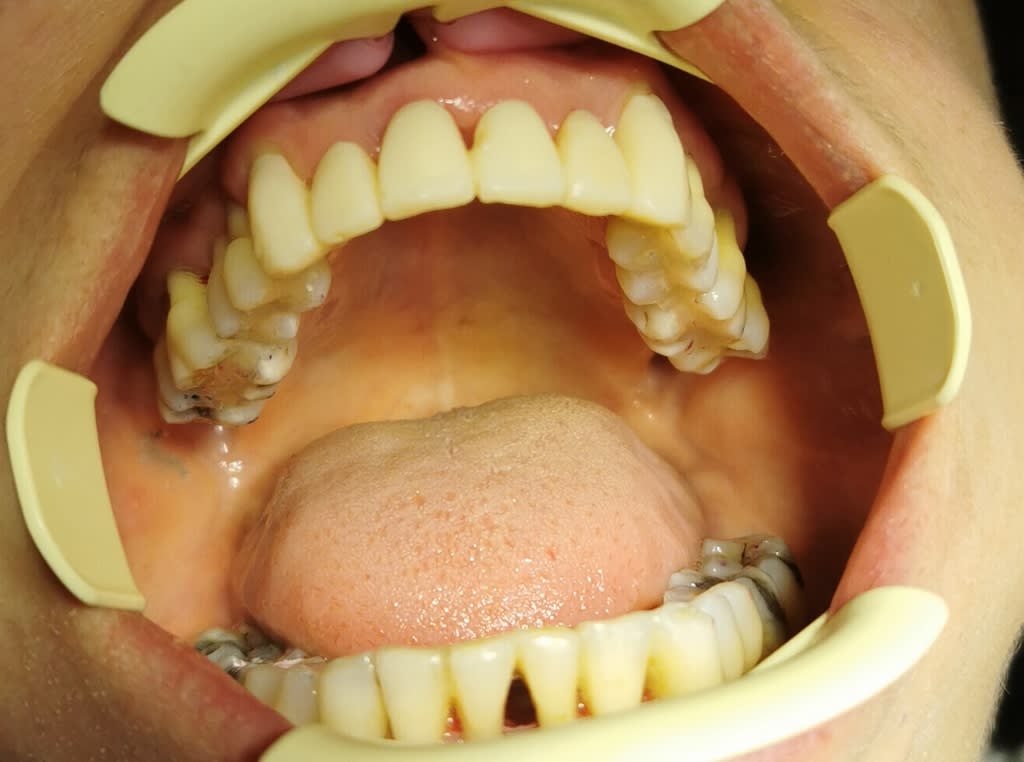

on avance, la patiente est appliquée et commence à gérer le brossage

les différents traitements (endo, détartrages, curetage des poches, bétadine et birodogyl 20 jours, commencent à porter leurs fruits, plus de suintements purulent ...et réduction de la mobilité ...

taille du haut et "bridge" complet provisoire en résine d'après le wax-up...

si tout est "calme" prochaine étape armature métal de contention qui sera recouverte d'Emax press.

mais d'abord quels soins à finir.. ...